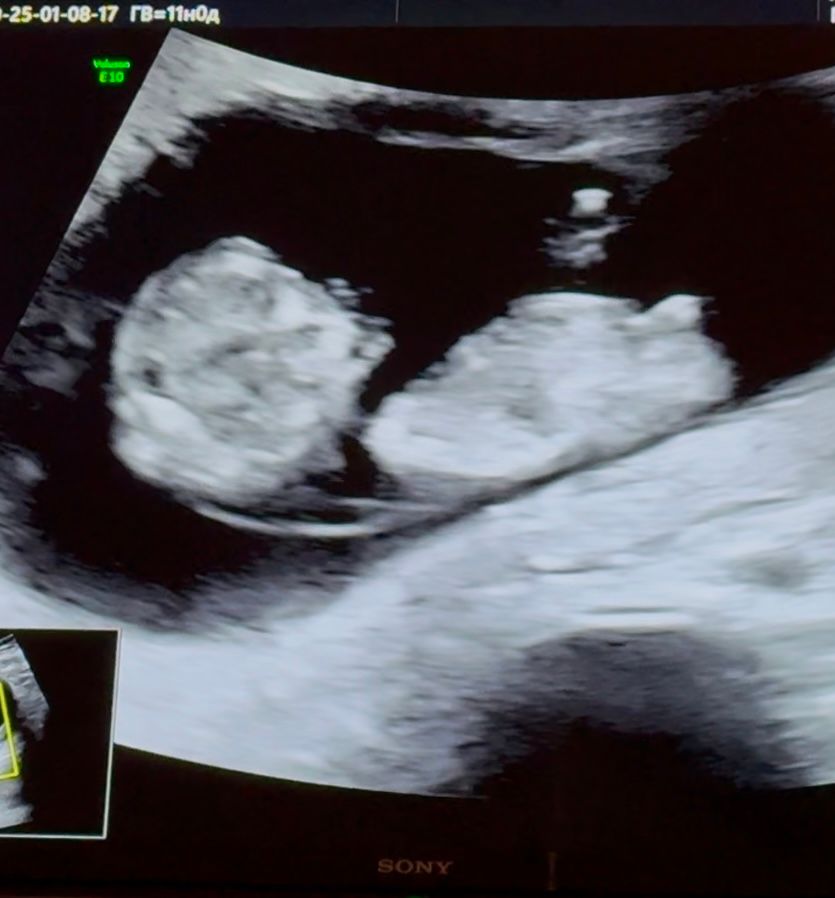

Девочки, всем привет) понимаю, что еще очень рано, но срок 11 недель, сегодня пошла на узи, так как резко пропал токс и что-то испугалась) пошла на узи, с лялькой все ок, я спросила про пол, мне сказала узистка, что пока не особо берется определять срок) но у меня есть фото с узи, как думаете, кто разбирается в узи, кто там?) Прошу не кидайте в меня тапками, просто интересно же )

Мне кажется параллельно-девочка

У моих пацанов по-другому на этом сроке было